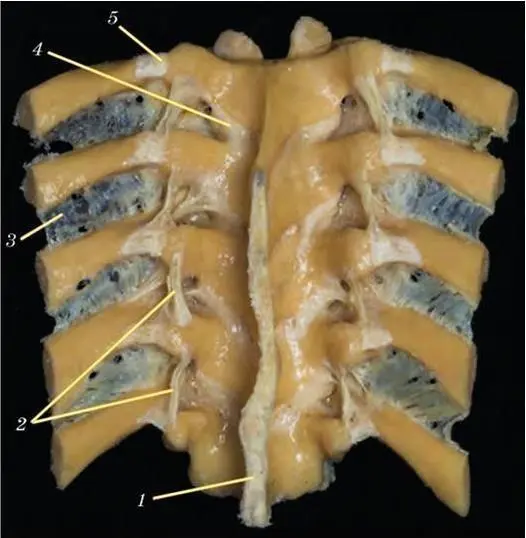

Рис. 43. Соединения позвонков.Натуральный анатомический препарат. Полимерное бальзамирование. Вид сзади:

1— надостистая связка; 2 – межпоперечная связка; 3 – межреберная мембрана; 4 – желтая связка; 5— реберно-поперечный сустав

К позвоночному столбу прикрепляются ребра. При этом головка ребра прикрепляется к телу позвонка, а бугорок ребра соединяется с поперечным отростком (см. рис. 42, 43). На данных рисунках хорошо виден сустав головки ребра, укрепленный лучистой связкой, и реберно-поперечный сустав, укрепленный реберно-поперечными связками.

Обратите внимание, что задний конец ребра образует два сустава, которые окружены большим количеством связок. Эти соединения очень прочные и при травмах никогда не бывает отрывов ребра от позвонка или переломов его заднего конца. Как правило, происходит перелом тела ребра (см. рис. 33). Суставы между ребром и позвонком очень тугие, в них часто возникают артрозо-артриты. При этом ребро срастается с позвонком. Естественно, данные процессы вызывают боли, так как в результате сужения межпозвоночных отверстий сдавливаются корешки спинномозговых нервов. Кроме того, срастание ребер с позвонками сопровождается нарушением дыхания. Для осуществления нормального дыхания ребра должны совершать в суставах вращение, при котором поднимаются и опускаются их передние концы (расширяется и сужается грудная клетка). При артрозо-артритах ребернопозвоночных суставов дыхание становится брюшным.